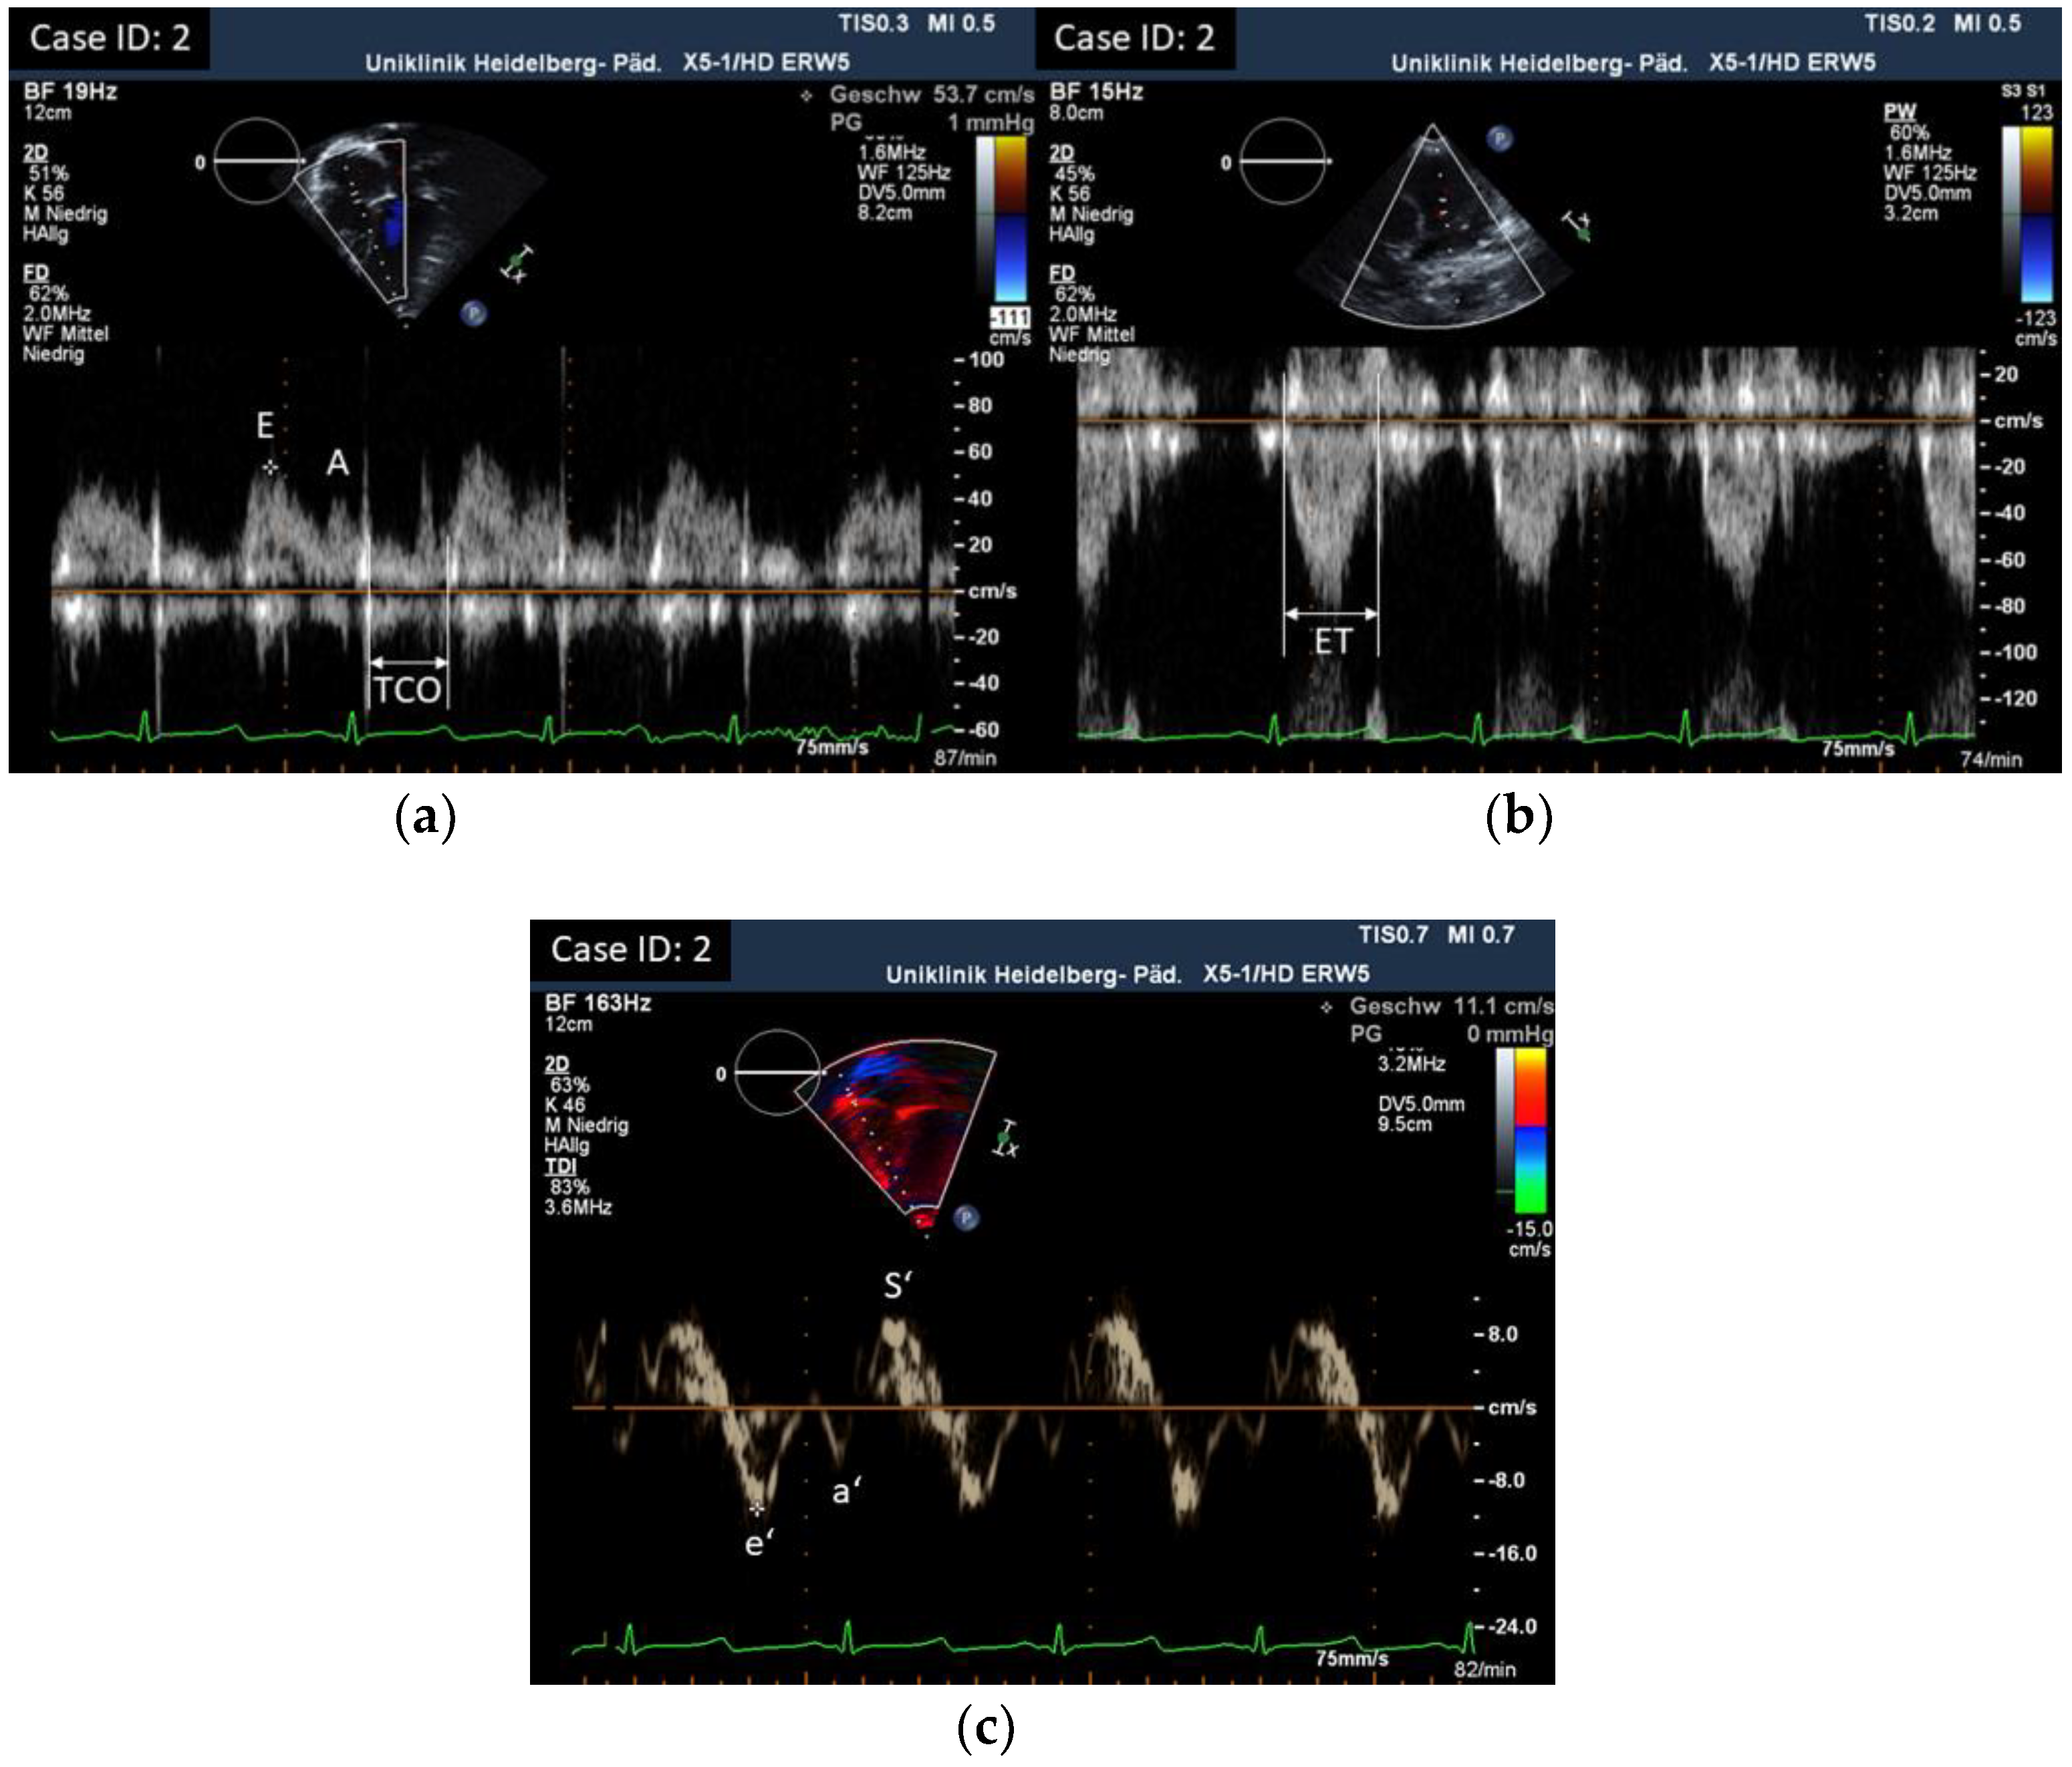

| ID | TV E Vmax cm/s | TV A Vmax cm/s | TV E/A | TV e’ Vmax cm/s | TV a’ Vmax cm/s | TV e’/a’ (adult) | TV E/e’ |

| 1 | 55 | 32 | 1.7 | 15.5 | 8 | / | 3.5 |

| 2 | 54 | 38 | 1.4 | 11 | 5.3 | / | 4.9 |

| 3 | 49 | 36 | 1.36 | 14 | 9.4 | / | 3.5 |

| 4 | 55 | 44 | 1.3 | 14 | 12 | / | 3.9 |

| 5 | 62 | 42 | 1.5 | 10.4 | 5.9 | / | 5.96 |

| 6 | 55 | 32 | 1.7 | 11 | 7.3 | 1.5 | 5 |

| 7 | 75 | 73 | 1 | 8.5 | 7 | / | 8.82 |

| 8 | 53 | 45 | 1.2 | 14.3 | 9.52 | / | 3.7 |

| 9 | 75 | 54 | 1.4 | 20.1 | 19 | 1.05 | 3 |

| 10 | 60 | 46 | 1.3 | 20 | 11 | / | 3 |

| 11 | 67.6 | 96.3 | 0.7 | 13.5 | 21.9 | / | 5 |

| 12 | 63 | 38 | 1.7 | 12.4 | 10.2 | 1.22 | 5.1 |

| 13 | 59 | 41.8 | 1.4 | 10.7 | 7.1 | 1.51 | 5.5 |

| 14 | 55.8 | 57.8 | 0.97 | 9.5 | 4.7 | / | 5.87 |

| 15 | 49.4 | 42.9 | 1.2 | 7.46 | 5.3 | 1.41 | 6.62 |

| 16 | 82 | 45 | 1.8 | 11.7 | 9.3 | 1.26 | 7 |

| 17 | 55 | 34.8 | 1.58 | 11 | 9.2 | / | 5 |

| 18 | 85 | 65.8 | 1.3 | 15.8 | 6.9 | / | 5.4 |

| Parameter | n | Mean | SD | 25% | Median | 75% | Min | Max |

|---|---|---|---|---|---|---|---|---|

| TV E/A | 18 | 1.36 | 0.29 | 1.22 | 1.38 | 1.56 | 0.70 | 1.80 |

| TV E/e’ | 18 | 5.04 | 1.51 | 3.75 | 5.00 | 5.78 | 3.00 | 8.82 |